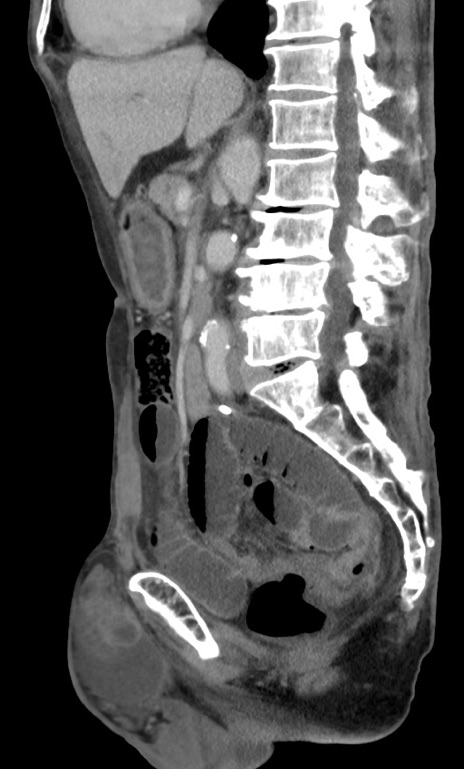

症例3(矢状断像)

【症例】 70歳代男性

【主訴】右鼠径部腫瘤、疼痛

【現病歴】本日朝より上記主訴あり、受診。

【既往歴】膀胱癌にて膀胱全摘、両側尿管皮膚瘻

【データ】WBC 5600、CRP 0.56